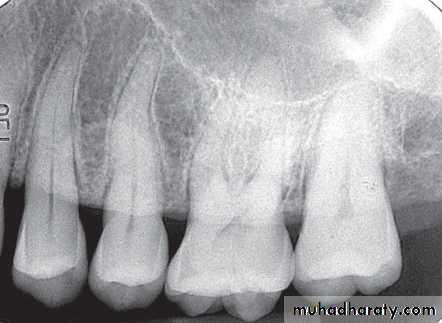

Radiographic features:

Location: *posterior mandible.Periphery: Better defined than the acute phase. In acute exacerbation periphery is radiolucent.

Internal structure: Lesion is more radiopaque and may be equivalent to cortical bone. Small regions of radiolucency may be scattered .

Effects on surrounding structures: New periosteal bone in series of radioqaue lines (onion skin) parallel to the cortical bone surface.

Apical widening of PDL space of non- vital tooth.

Well –defined break in outer cortex (draining fistula).